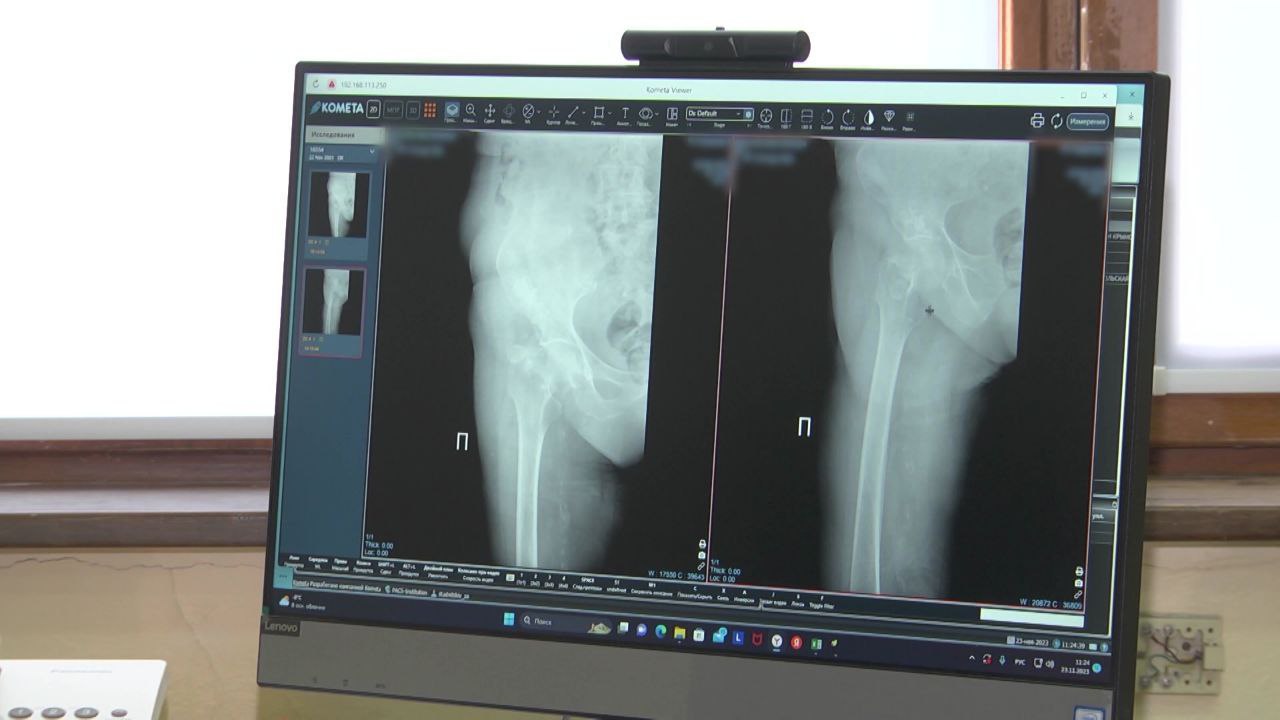

Вячеслав Гладков рассказал о замечаниях жителей, ожидающих операции по эндопротезированию

Основные претензии касаются плохой обратной связи со стороны Министерства здравоохранения.

«Конечно же, такие замечания недопустимы. Будем отрабатывать в каждом случае и вносить изменения в систему обратной связи и усиление контроля по каждому обращению», – подчеркнул губернатор.

Ранее глава региона инициировал опрос среди белгородцев, стоящих в очереди на замену суставов. Жителей просят рассказать о времени ожидания, изменениях за последние полгода, продвижении в очереди и дате назначения операции.